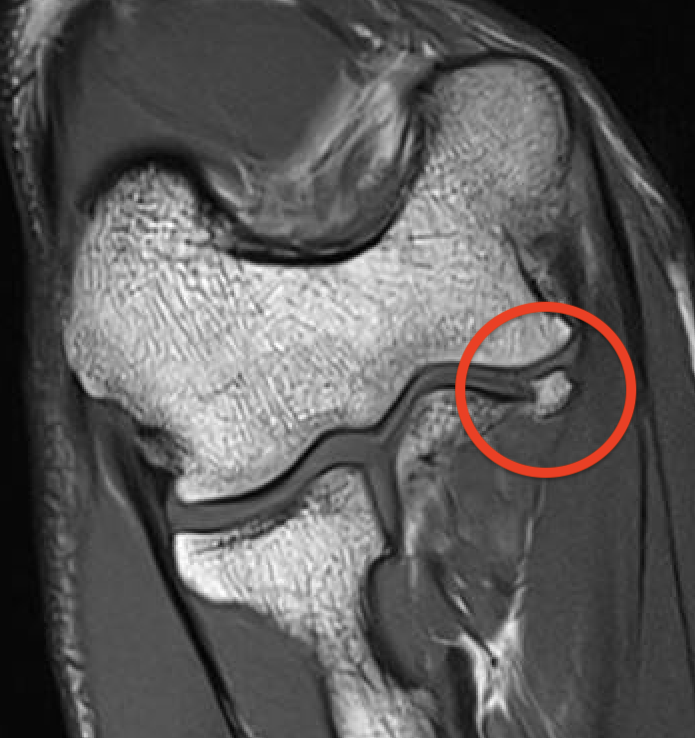

MRI

Intact

Grading of tears

Proximal / midsubstance / distal injury

Partial tears - low grade versus high grade

Complete tears

Acute full thickness UCL tear

High grade partial distal UCL tear

Bony avulsion UCL complex medial epicondyle

Bony avulsion UCL sublime tubercle